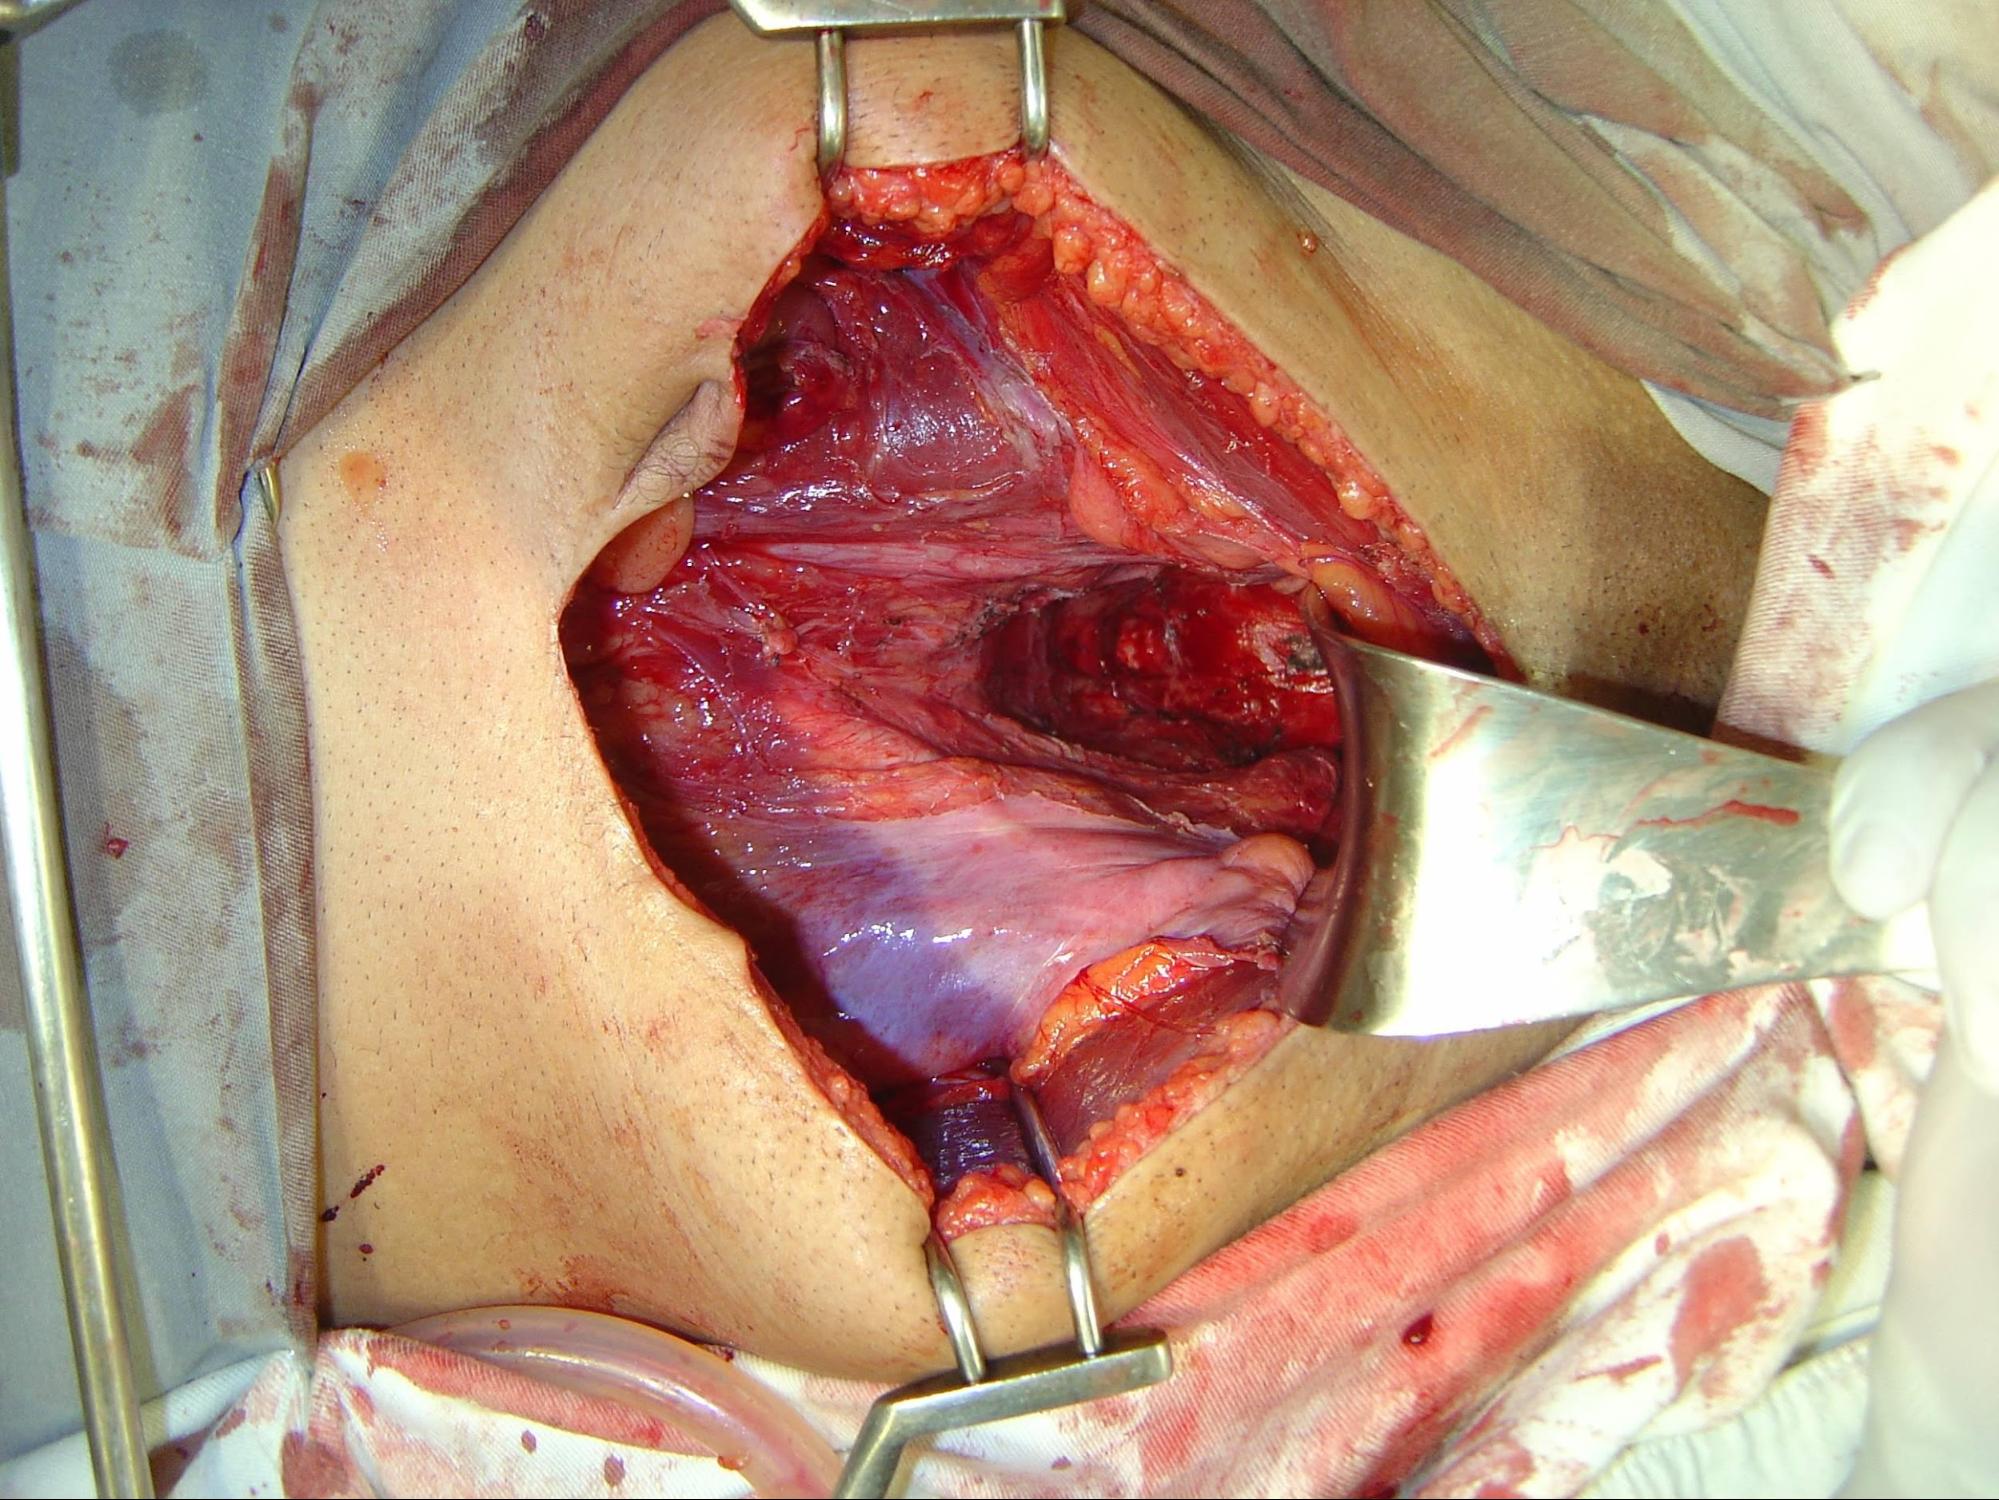

Aspecto da pelve após retossigmoidectomia com excisão total do mesorreto, cirurgia padrão para tratamento de tumor de reto: (associado à fotografia abaixo)

Foto: cirurgia realizado pelo Dr. Claudio Quadros.